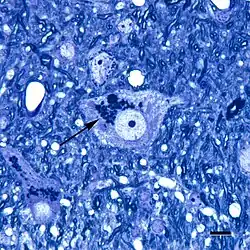

Lipofuscin is the name given to fine yellow-brown pigment granules composed of lipid-containing residues of lysosomal digestion.[1][2] It is considered to be one of the aging or "wear-and-tear" pigments, found in the liver, kidney, heart muscle, retina, adrenals, nerve cells, and ganglion cells.[3]

Lipofuscin appears to be the product of the oxidation of unsaturated fatty acids and may be symptomatic of membrane damage, or damage to mitochondria and lysosomes. Aside from a large lipid content, lipofuscin is known to contain sugars and metals, including mercury, aluminium, iron, copper and zinc.[4] Lipofuscin is also accepted as consisting of oxidized proteins (30–70%) as well as lipids (20–50%).[5] It is a type of lipochrome[6] and is specifically arranged around the nucleus.

In the peripheral nervous system, abnormal accumulation of lipofuscin known as lipofuscinosis[1] is associated with a family of neurodegenerative disorders – neuronal ceroid lipofuscinoses, the most common of these is Batten disease.

Also, pathological accumulation of lipofuscin is implicated in Alzheimer's disease, Parkinson's disease, amyotrophic lateral sclerosis, certain lysosomal diseases, acromegaly, denervation atrophy, lipid myopathy, chronic obstructive pulmonary disease,[16] and centronuclear myopathy. Accumulation of lipofuscin in the colon is the cause of the condition melanosis coli.